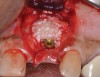

(4.) The implant in the molar position was relatively narrow and failed biomechanically. It was removed with a trephine, and the adjacent fractured bicuspid was also extracted to accommodate an implant. Because sufficient apical bone was present, a wider implant was placed in the molar position. Bone augmentation was performed around both implants.

Figure 4

(5.) The implant in the molar position was relatively narrow and failed biomechanically. It was removed with a trephine, and the adjacent fractured bicuspid was also extracted to accommodate an implant. Because sufficient apical bone was present, a wider implant was placed in the molar position. Bone augmentation was performed around both implants.

Figure 5